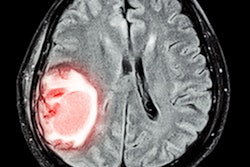

Scans of a stroke patient's brain show the area where tissue has died (magenta) and where tissue is damaged but may still be saved with prompt intervention (green). Image courtesy of Dr. Akash Kansagra.Kansagra and colleagues had access to a data repository of 231,753 patients whose scans were analyzed with the Rapid software, and they calculated the number of scans performed on a daily basis from July 2019 through April 27, 2020. In particular, they compared daily use of Rapid during a 29-day period before the pandemic in February 2020 with a 14-day period from March 26 to April 8.